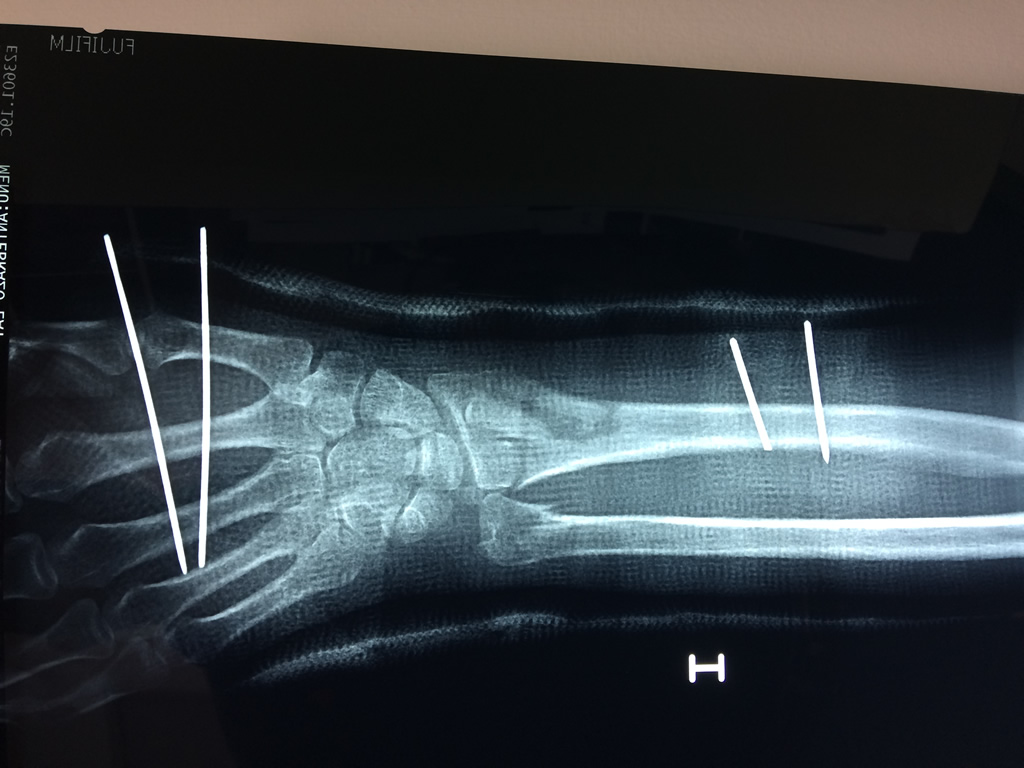

Húmero - Cirugías de Muñecas y Manos

Los procedimientos más comunes en cirugía de la mano son aquellos destinados a reparar traumatismos, incluyendo lesiones de tendones, nervios, vasos sanguíneos, y articulaciones; huesos fracturados; y quemaduras, cortes, y otros daños de la piel.